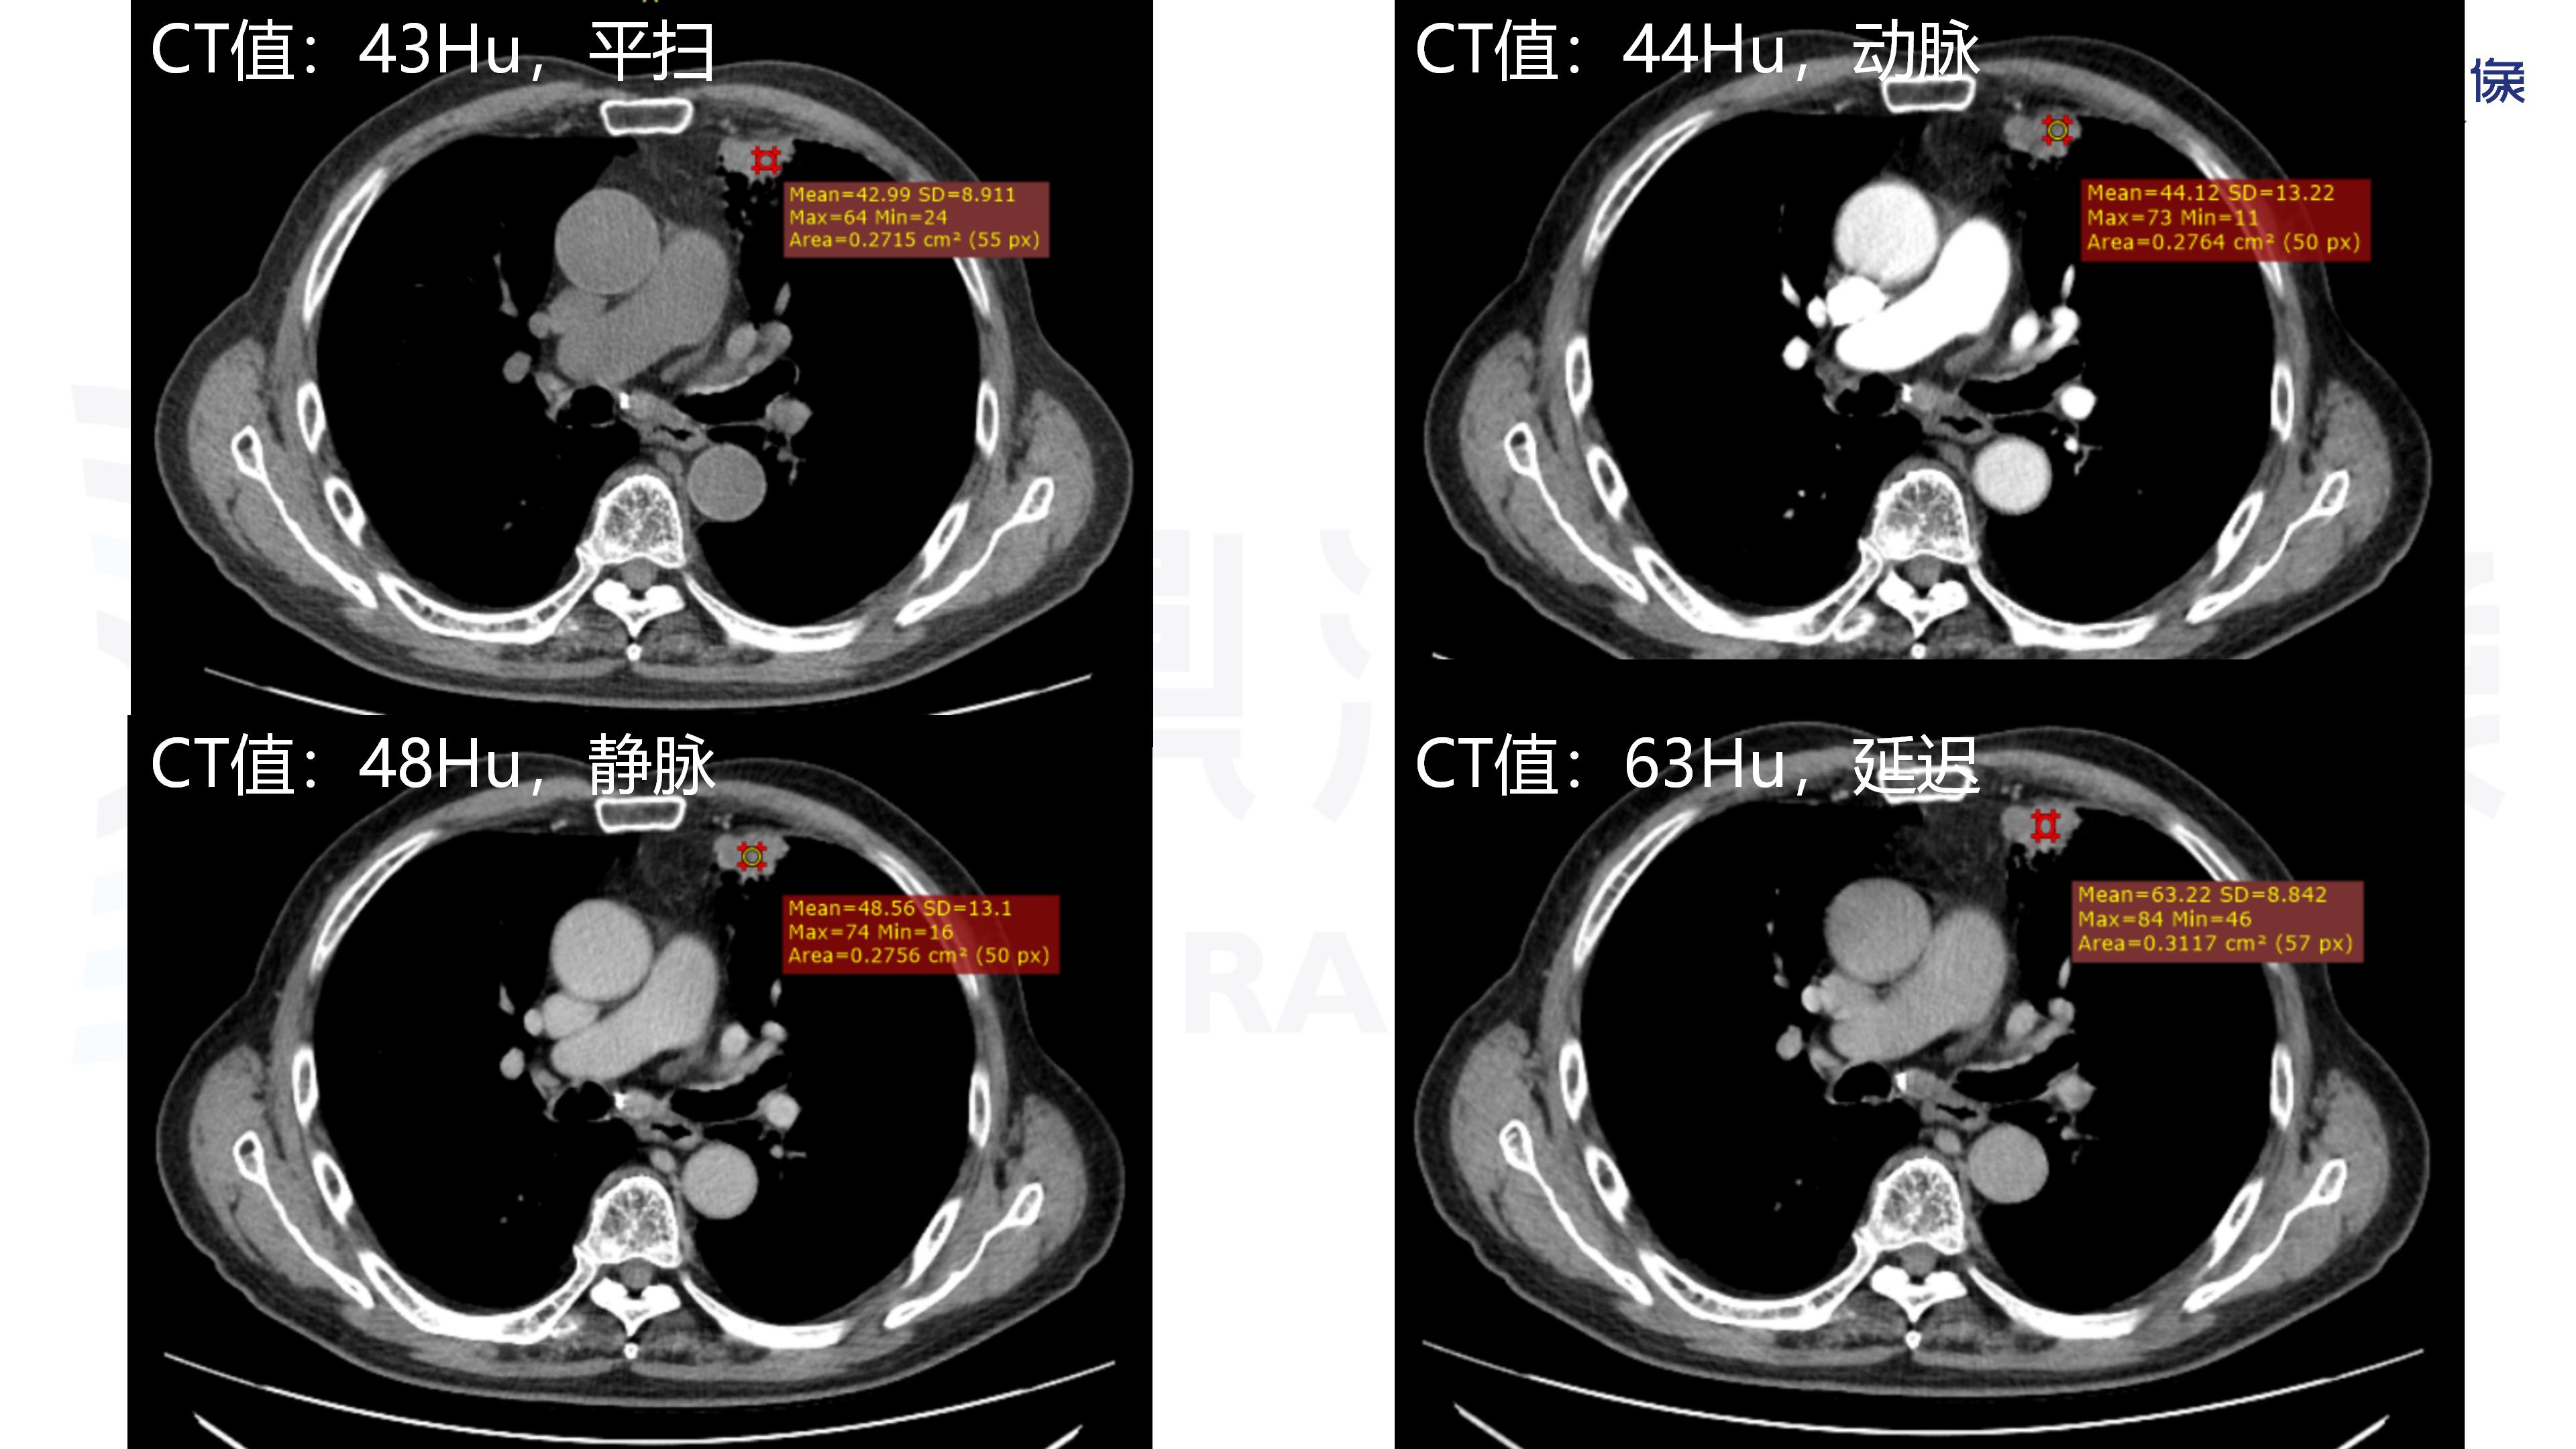

肺腺癌-鼎湖社群读片病例